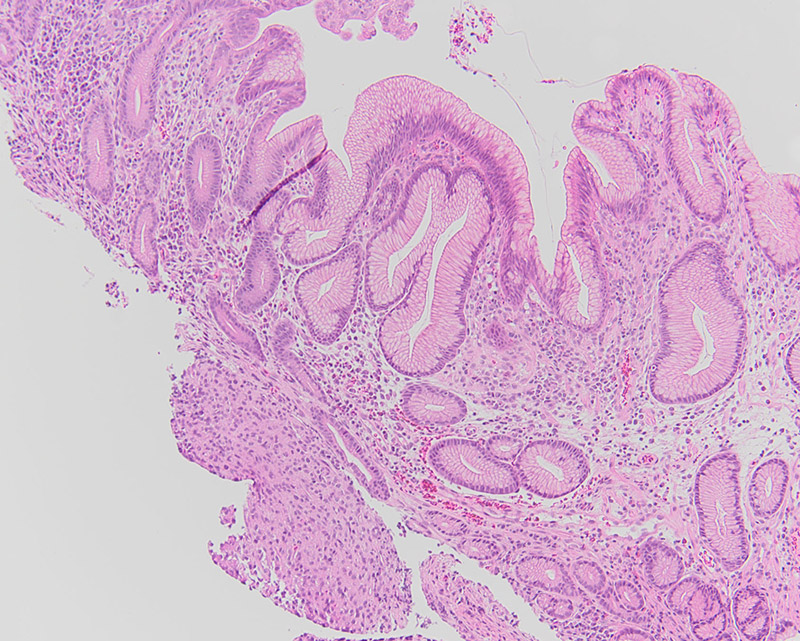

Initial laboratory work up demonstrated that the patient was anemic (Hgb = 4.5 g/dL), with WBC and platelet count within normal limits. CT scan revealed two exophytic masses originating from the greater curvature of the stomach at the antrum with intra and extraluminal components (Figure 1). Upper endoscopy noted a few small, smooth sessile polyps in the gastric antrum. One large ulcerated polyp was noted close to the pylorus.

The polyp was non-obstructing and not actively bleeding; biopsies were taken of this polyp. Histologically the biopsy specimen demonstrated a proliferation of uniform mixed epithelioid and spindle-epithelioid cells amongst antral-type mucosa (Figures 2, 3). No significant pleomorphism or mitotic figures were identified. Immunohistochemical stains for DOG1 and c-Kit (CD117) were positive (Figures 4 and 5, respectively). A subsequent wedge resection of the stomach to include the lesions was performed and confirmed the original biopsy diagnosis (Figure 6). Molecular testing for c-Kit and PDGFRA were performed and were negative.